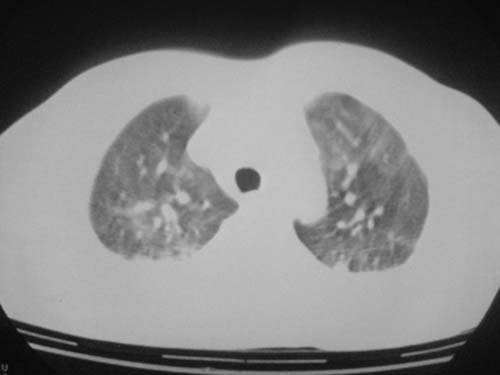

外伤病人,年龄忘了,中年人右侧肋骨骨折了,

这是刚住院拍的片子。